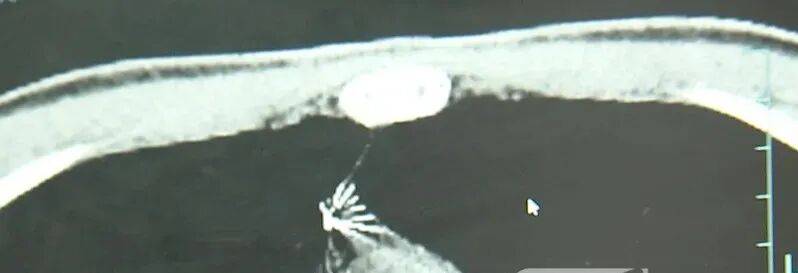

近日,安徽17岁小伙小陆参加征兵体检,胸片结果显示:胸腔内有一处金属高密度影,形态细长,像一根针比特币下载。

进一步的CT检查确认,异物是一枚金属针,斜插在肺组织内,位置十分凶险比特币下载。

杭州市第一人民医院心胸外科副主任冯兴说:“我们看到这个针的尖锐部,正好指向他体内的一个大血管,边上是上腔静脉和胸主动脉,因此这个针稍有不慎,就有可能造成周边血管的损伤,甚至危及生命比特币下载。”